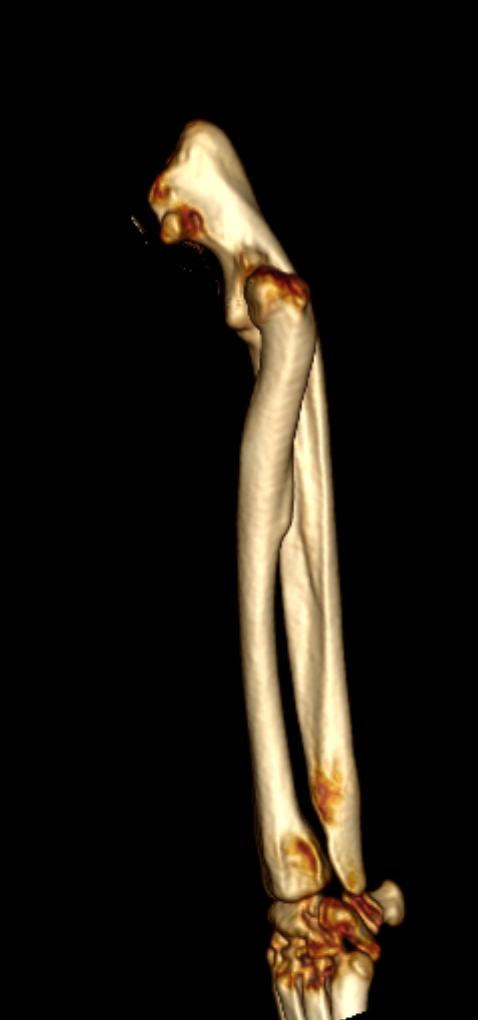

2歳の柴犬ちゃんが、生まれてすぐに痛めた肘に徐々に痛みが出てきたとのことで、主治医から診察と必要があれば手術をして欲しいと連絡がありました。CTでは橈骨頭が外側に脱臼して変位していました。また回転性の変形を伴っています。同時に尺骨にも湾曲が認められています。このような変形矯正には3Dプリンターで模擬手術を行いあらかじめシミュレーション手術をしておくと時間の短縮と正確な変形矯正が可能となります。このようなテクノロジーを動物医療にもどんどん取り入れていきたいと思います。また、骨きり部位にはPRFと自家海綿骨移植を行い治癒促進を期待します。